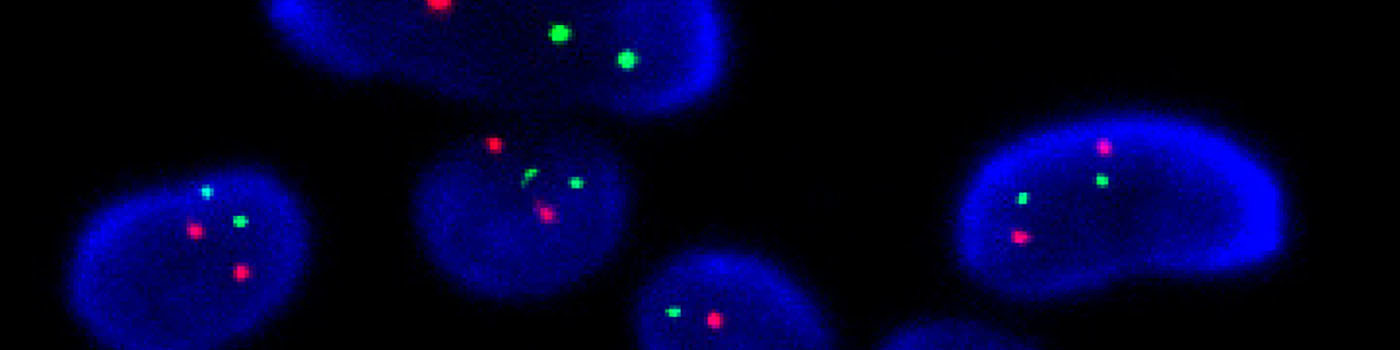

Close-up of a group of nuclei including gene probes.

To determine the HER2/CEN-17 ratio, the total number of HER2 signals (Red) and the number of CEN-17 (Green) signals in the same 20 nuclei are identified. The total number of HER2 signals is then divided by the number of CEN-17 signals. Ratios above 2 are classified as amplified whereas ratios below 2 are classified un-amplified. Caution should be taken when intepreting on results near the cut-off (1.8 – 2.2). The operator only needs to define an overall region of interest.